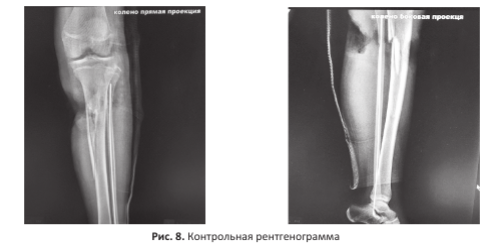

Вид конечности на следующие сутки, результаты пульсоксиметрии, ЦДС и контрольная рентгенограмма представлены на рисунках 6-8.